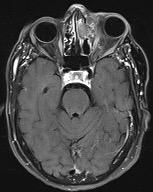

Sjúklingur er áberandi úteygð (exopthalmos) og með hliðartilfærslu á vinstra auga (mynd 1a). Við mat á heilataugum III, IV og VI kemur fram að sjúklingur á erfitt með að horfa upp og tvísýni versnar þegar hún horfir upp og til hægri. Lífsmörk eru innan viðmiðunarmarka og önnur líkamsskoðun ómarkverð.

a) MRI mynd af höfði sjúklings fyrir aðgerð. Vinstra auga er útstætt vegna fyrirferðar slímblöðrunnar.

b) Þrívíddarmódel af höfuðkúpu sjúklings. Hér má sjá hvernig slímblaðran er vaxin í augntótt.

Fyrir aðgerðina var hannað módel með þrívíddarprentara (mynd 1b). Teknar voru tölvusneiðmyndir og segulsneiðmyndir sem stuðst var við í tölvustýrðri myndleiðsögn meðan á aðgerðinni stóð. Til að tryggja þétta lokun milli ne ols og heila og tilfærslu æðaríks ve ar á svæðið var notaður frír flipi. Sjúklingur fékk fræðslu um fyrirhugaða aðgerð og hugsanlega fylgikvilla. Gerður var skurður frá eyra til eyra (bicoronal) og húðinni af enni flett fram, niður að augntótt og superior orbital taugin frílögð. Beinplata yfir ennisblaði og augntótt var söguð frá og heilahimna losuð til að bæta aðgengi. Bakveggur ennisholu var arlægður og öll slímhúð beggja vegna hreinsuð burt. Beinþakið á augntóttinni var sagað laust og losað frá. Beinið, sem var afmyndað, var þynnt með demantsbor, sárið skolað og öll slímhúð á svæðinu arlægð Í kjölfarið var augntóttin endurgerð með beingröftum. Skorinn var upp fremri lærisflipi (anterolateral thigh flap) samsettur úr vöðvafelli og litlum vöðvabita frá vastus lateralis og tengdur á sameiginlegum æðastilk frá circumflex femoralis æðinni (mynd 2). Flipinn var síðan staðsettur ofan við endurgerða augntóttina og vöðvabitinn lagður inn í ne olið. Í gegnum holu í ennisbeininu var æðastilkurinn frá flipanum þræddur út. Með aðstoð smásjár var gagnaugaæðin (temporal artery) saumuð saman með Ethylon 9.0 og bláæðin tengd með 2,5 mm hring áföstum doppler til að hægt væri að fylgjast með blóðflæði til og frá flipanum fyrstu dagana eftir aðgerð Beinplatan frá ennisblaði var síðan fest aftur með þunnum járnplötum og skrúfum, húðinni flett yfir svæðið, sinafell saumað og húð heftuð saman. Á mynd 3 má sjá sárið fyrir og eftir ígræðslu flipans. Aðgerðartími var um 6 klukkustundir.

Bataferlið gekk vel og sjúklingur losnaði við tvísýni og höfuðverkjaköst. Á mynd 4 sést hvernig úteygða og tilfærsla á vinstra auga gekk nánast alveg til baka. Líðan og lífsgæði sjúklings bötnuðu til muna.

a) MRI mynd af höfði sjúklings eftir aðgerð. Slímblaðran er horfin og augntótt komin í eðlilega stöðu.

b) Ljósmynd af augum sjúklings. Úteygða og tilfærsla á vinstra auga er gengin til baka.